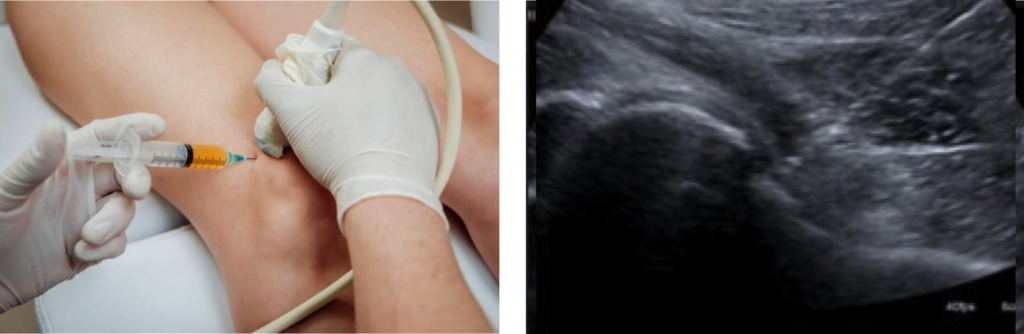

L’artrosi è una condizione cronica che evolve lentamente e, senza un trattamento adeguato, può compromettere seriamente la mobilità e la qualità della vita. Se trattata tempestivamente con soluzioni terapeutiche moderne, come la radiologia interventistica con tecniche minimamente invasive, è possibile ridurre il dolore e migliorare la funzionalità articolare.